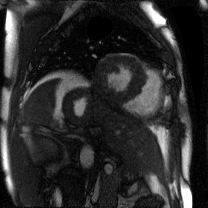

Supervised Deep-Learning (DL)-based reconstruction algorithms have shown state-of-the-art results for highly-undersampled dynamic Magnetic Resonance Imaging (MRI) reconstruction. However, the requirement of excessive high-quality ground-truth data hinders their applications due to the generalization problem. Recently, Implicit Neural Representation (INR) has appeared as a powerful DL-based tool for solving the inverse problem by characterizing the attributes of a signal as a continuous function of corresponding coordinates in an unsupervised manner. In this work, we proposed an INR-based method to improve dynamic MRI reconstruction from highly undersampled k-space data, which only takes spatiotemporal coordinates as inputs. Specifically, the proposed INR represents the dynamic MRI images as an implicit function and encodes them into neural networks. The weights of the network are learned from sparsely-acquired (k, t)-space data itself only, without external training datasets or prior images. Benefiting from the strong implicit continuity regularization of INR together with explicit regularization for low-rankness and sparsity, our proposed method outperforms the compared scan-specific methods at various acceleration factors. E.g., experiments on retrospective cardiac cine datasets show an improvement of 5.5 ~ 7.1 dB in PSNR for extremely high accelerations (up to 41.6-fold). The high-quality and inner continuity of the images provided by INR has great potential to further improve the spatiotemporal resolution of dynamic MRI, without the need of any training data.

翻译:在这项工作中,我们建议了一种基于IRI的方法,用这种方法来改进动态磁共振感应成像(MRI)重建,而该方法只是以高度低劣的 k-空间数据为基础,而该数据仅以磁共振坐标作为投入。具体地说,拟议的IRI将动态MRI图像作为一种隐含功能来表示,并将其编码到神经网络中。网络的权重仅从稀有的(k, t)空间数据本身中学习,而没有外部培训数据集或先前的图像。 利用基于IRI的强有力隐含性稳定化,同时不以清晰的动态和时空坐标坐标坐标坐标坐标作为投入。 拟议的IRIR将动态MRI图像作为一种隐含功能,将其编码到神经网络中。网络的权重仅从淡化的(k, t)空间数据本身学习,而没有外部培训数据集或先前的图像。